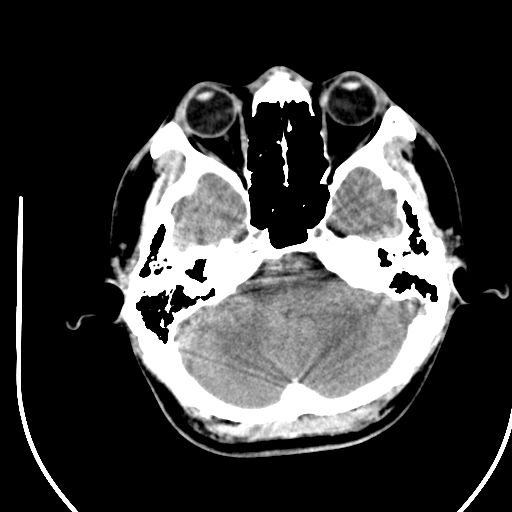

标题: CT28158:男,27Y。头痛数月,左顶叶血管瘤。 [打印本页]

标题: CT28158:男,27Y。头痛数月,左顶叶血管瘤。

考虑avm。

考虑avm。  建议dsa检查。

海绵状血管瘤

考虑左顶叶海绵状血管瘤,建议mr检查。

左侧额叶海绵状血管瘤可能性大;建议行mri检查。

考虑血管畸形,因其周可见水肿,不除外感染性病灶。建议mri检查。